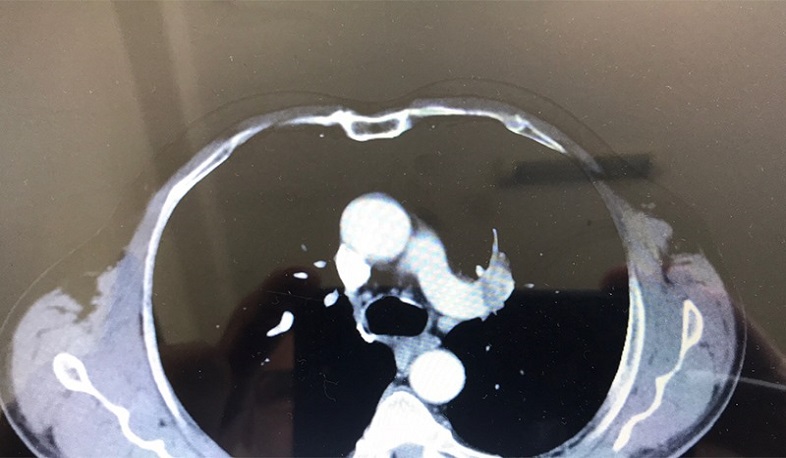

ԵՊԲՀ «Հերացի» թիվ 1 հիվանդանոցային համալիրի նյարդավիրաբուժության և գլխուղեղի կաթվածների վիրաբուժության մասնագիտացված կենտրոնում նյարդավիրաբույժներ Սևակ Բադայանը և Լեռնիկ Գրիգորյանը կատարել են առաջային կապակցող զարկերակի պատռված պարկաձև անևրիզմայի ներանոթային միկրոպարույրներով օբլիտերացիա՝ COVID-19 հիվանդությամբ՝ թոքաբորբ ունեցող հիվանդին։

49-ամյա հիվանդն անգիտակից վիճակում շտապօգնության մեքենայով տեղափոխվել էր «Գորիսի» բժշկական կենտրոն: Կատարված գլխուղեղի և կրծքավանդակի ԿՏ քննությումբ հայտնաբերվել էր սուբարախնոիդալ, ներփորոքային արյունազեղում: Նախապես կապ հաստատելով «Հերացի» համալսարանական հիվանդանոցի նյարդավիրաբուժական ծառայության հետ՝ հիվանդին Գորիսից սանավիացիայով տեղափոխել են Երևան և շտապօգնությամբ հասցրել համալսարանական հիվանդանոց՝ վիրահատական բուժման նպատակով: Շտապ կարգով կատարվել է գլխուղեղի և կրծքավանդակի ԿՏ քննություն, գլխուղեղի ԿՏ-անգիոգրաֆիա, որով հայտնաբերվել է առաջային կապակցող զարկերակի պատռված պարկաձև անևրիզմա, շուրջը՝ ծավալուն սուբարախնոիդալ արյունազեղում։

Բժիշկներ Սևակ Բադայանին և Լեռնիկ Գրիգորյանին գրեթե երեք ժամ տևած վիրահատության արդյուքնում հաջողվեց կատարել առաջային կապակցող զարկերակի պատռված անևրիզմայի էնդովասկուլյար օբլիտերացիա միկրոպարույրներով: Հաշվի առնելով հիվանդի մոտ COVID-19 ՊՇՌ քննության դրական արդյունքը՝ նախապես կապ է հաստատվում առողջապահության նախարարության, ինչպես նաև «Սուրբ Գրիգոր Լուսավորիչ» բժշկական կենտրոնի ռեանիմացիոն ծառայության ղեկավարության հետ, որից հետո հիվանդը տեղափոխվում է «Սուրբ Գրիգոր Լուսավորիչ» ԲԿ՝ հետագա բուժումը շարունակելու նպատակով։ Դեղորայքային բուժումից հետո կատարվում է ՊՇՌ կրկնակի թեստավորում, և երկու բացասական արդյունք ստանալուց հետո հիվանդը կրկին տեղափոխվում է «Հերացի» թիվ 1 հիվանդանոց:

Հաշվի առնելով ստորին վերջույթների նոր առաջացած թուլությունը և կրկնված ԿՏ քննությամբ հակացուցումների բացակայությունը՝ հիվանդին կատարվում է կրկնակի ախտորոշիչ անգիոգրաֆիա սպազմոլիտիկների ներզարկերակային սելեկտիվ ներարկումով։ Հիվանդը վիրահատությունից հետո էքստուբացվել է և բուժումը մասնագիտացված վերականգնողական կենտրոնում շարունակելու նպատակով օրեր անց դուրս գրվել բարելավումով՝ գիտակից, ինքնուրույն շնչառությամբ, խոսքի արտաբերման և խոսքը հասկանալու ֆունկցիայի պահպանումով, ստորին վերջույթների մնացորդային թուլությամբ՝ պայմանավորված պերիֆերիկ աքսոնալ պոլինեյրոպաթիայով: